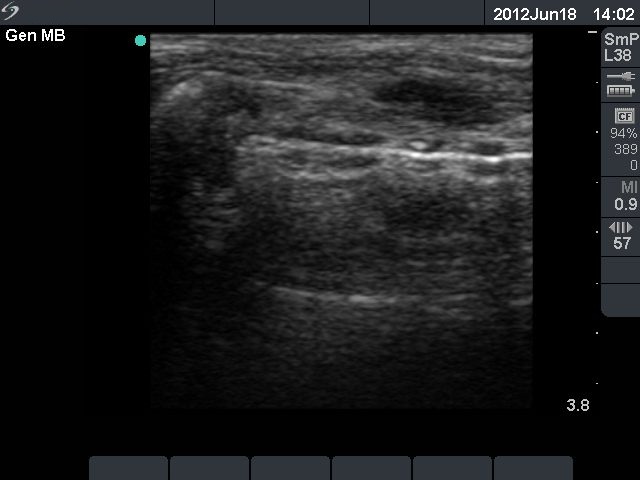

Second row: ultrasonographic picture before the second sclerotherapy. The size of the lesion was 38x28x39 mm (width x depth x length).